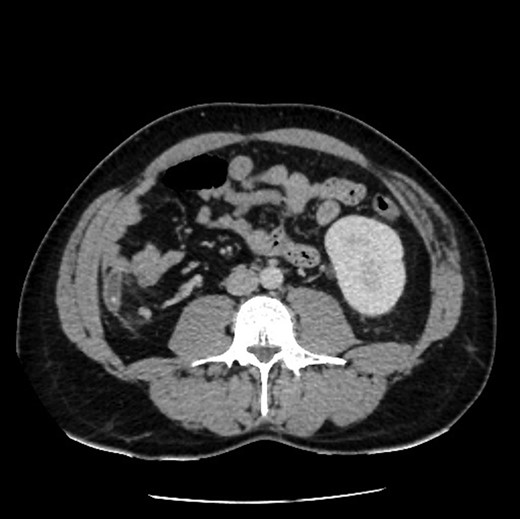

Axial view showing absence of right kidney due to congenital agenesis. Appendicitis with faecolith.